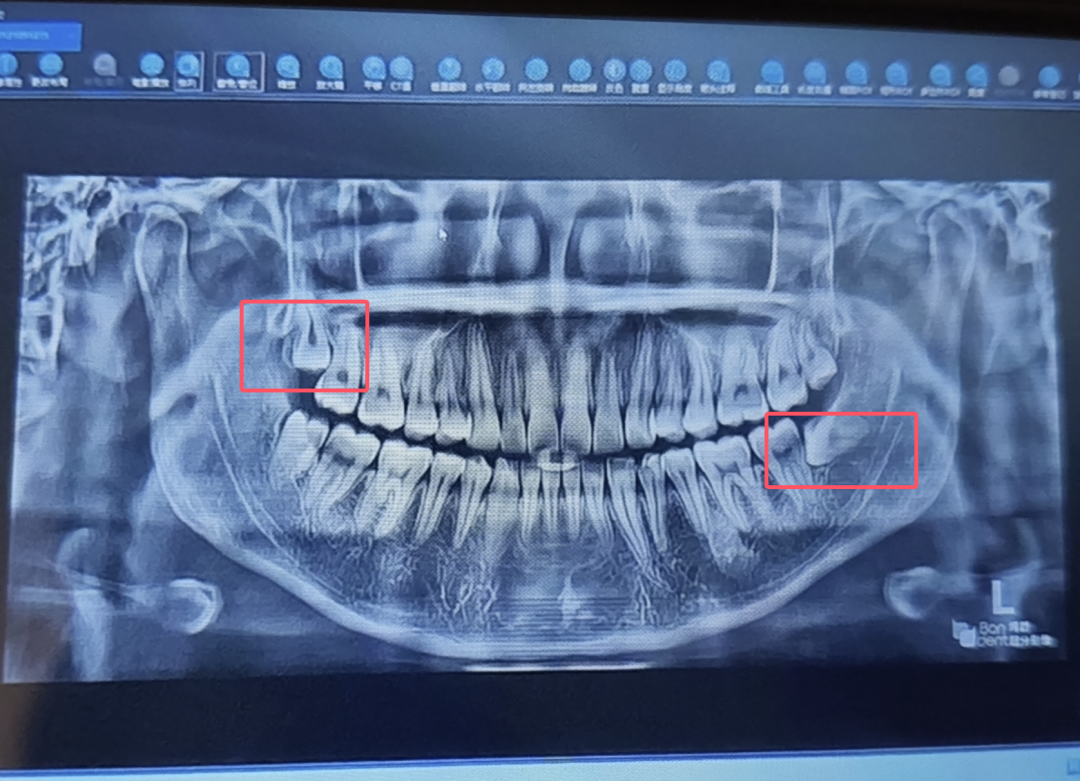

但不要觉得上图这种智齿是很严重的,相反那是最轻的,好歹都算萌出了,没办法萌出的智齿一大堆,甚至因为空间不足导致横着长的都有,生长目标十分明确的对准第二恒磨牙的牙根,不把宝贵的第二恒磨牙顶死誓不罢休。

这种顶着第二恒磨牙横着长的智齿,不仅可以出现在一侧,还可能两侧都有。